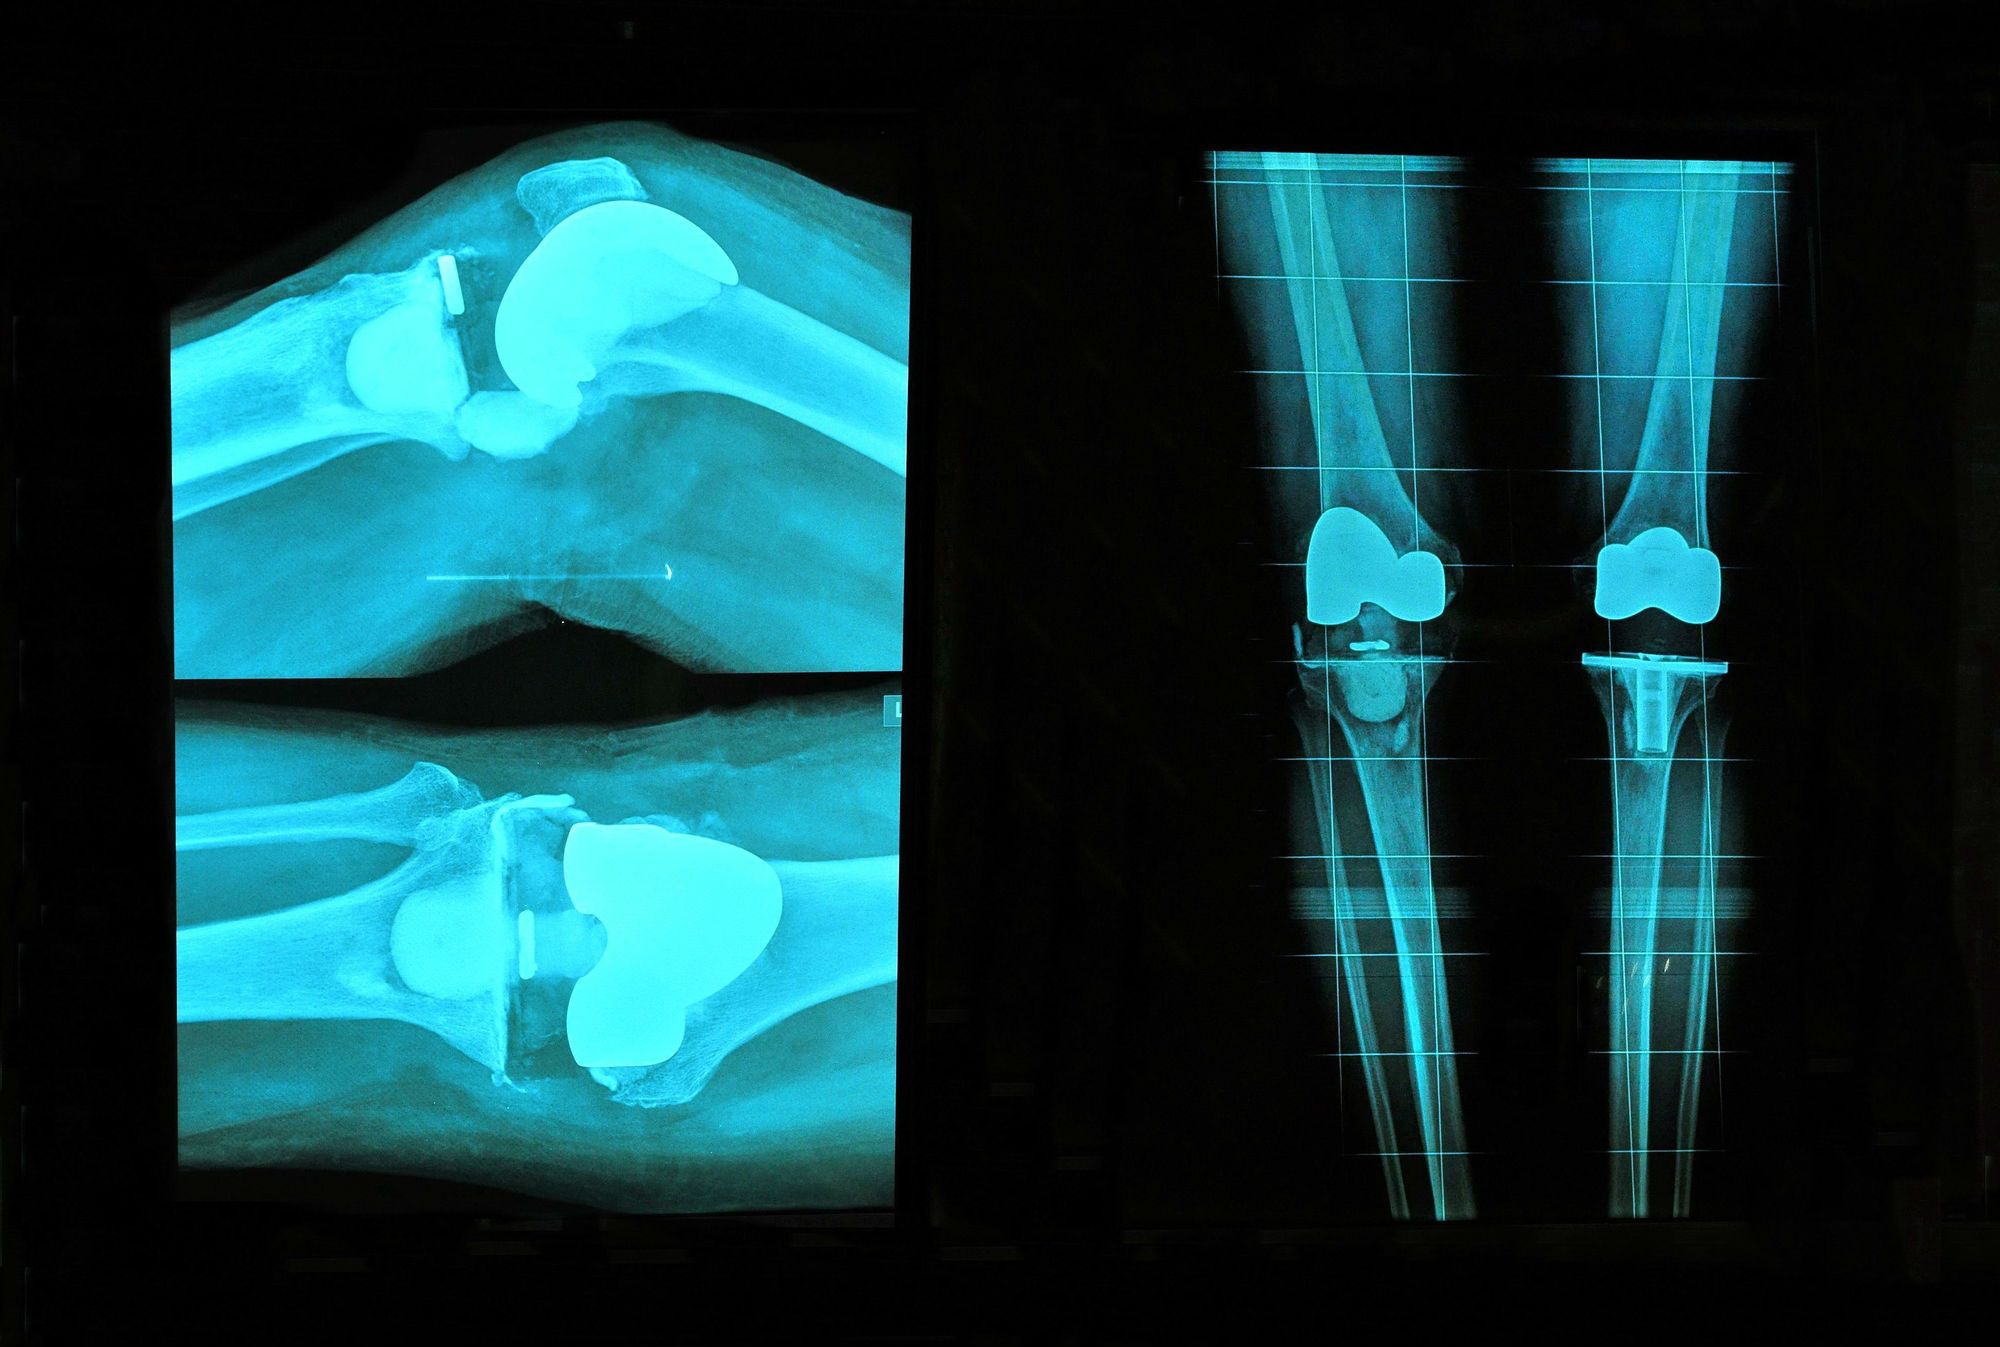

From www.researchgate.net

Radiographic images of a cemented total knee arthroplasty in the right What Is A Cement Knee Replacement The new bone grows into the spaces in the implant, holding it in. Cemented fixation uses a fast drying bone cement while uncemented fixation uses your existing bone to fit your new knee nice and snug. If a doctor has told you that you need a knee replacement, you probably have a lot of questions about what to expect. A. What Is A Cement Knee Replacement.